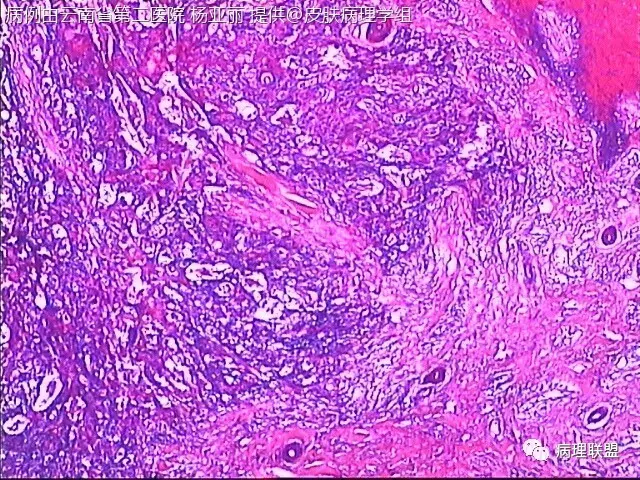

M/53 左手食指包块(皮肤鳞癌VS转移性鳞癌)

请各位老师帮忙看看,男性,53岁,左手食指包块 (病例由云南省第二医院 杨亚丽 提供,致谢!)

鳞癌没有问题。问题是否是转移癌:有否与表皮相连,病史演变如何?

@邓永键 谢谢邓主任,据说病人鼻子上有肿瘤才来切的手上的小包块,右手有,左手也有三四个,等我再问问鼻子上的是什么。看着细胞异型不明显,生长方式倒是确实不好。第6图有和表皮的关系,不相连,邓老师,鼻子上的肿瘤确实是鳞癌,这么说来手上的是转移的就很合理了。邓主任真是高,佩服!